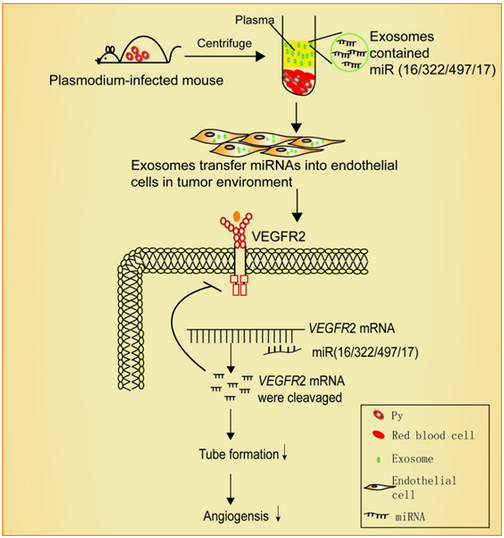

记者6月21日获悉���,南京传奇生物科技有限公司与西安交通大学第二附属医院合作展开的多靶点CAR-T疗法临床试验表现出惊人的客观缓解率,在近日举行的美国临床癌症学会年会上��,该疗法引起与会专家的高度评价和瞩目�。“患病后��,人体免疫细胞无法识别肿瘤细胞��,导致肿瘤快速复制转移病情扩散”���,南京传奇生物科技有限公司首席科学家兼创始人范晓虎说����,这种CAR-T疗法的特点是双靶点治疗,“目前大多数CAR-T疗法是一个靶点����,就像用一只手去抓球极易脱手,而双靶点相当于两只手去抓球����,成功率大大增加”。多发性骨髓瘤是三大血液系统恶性肿